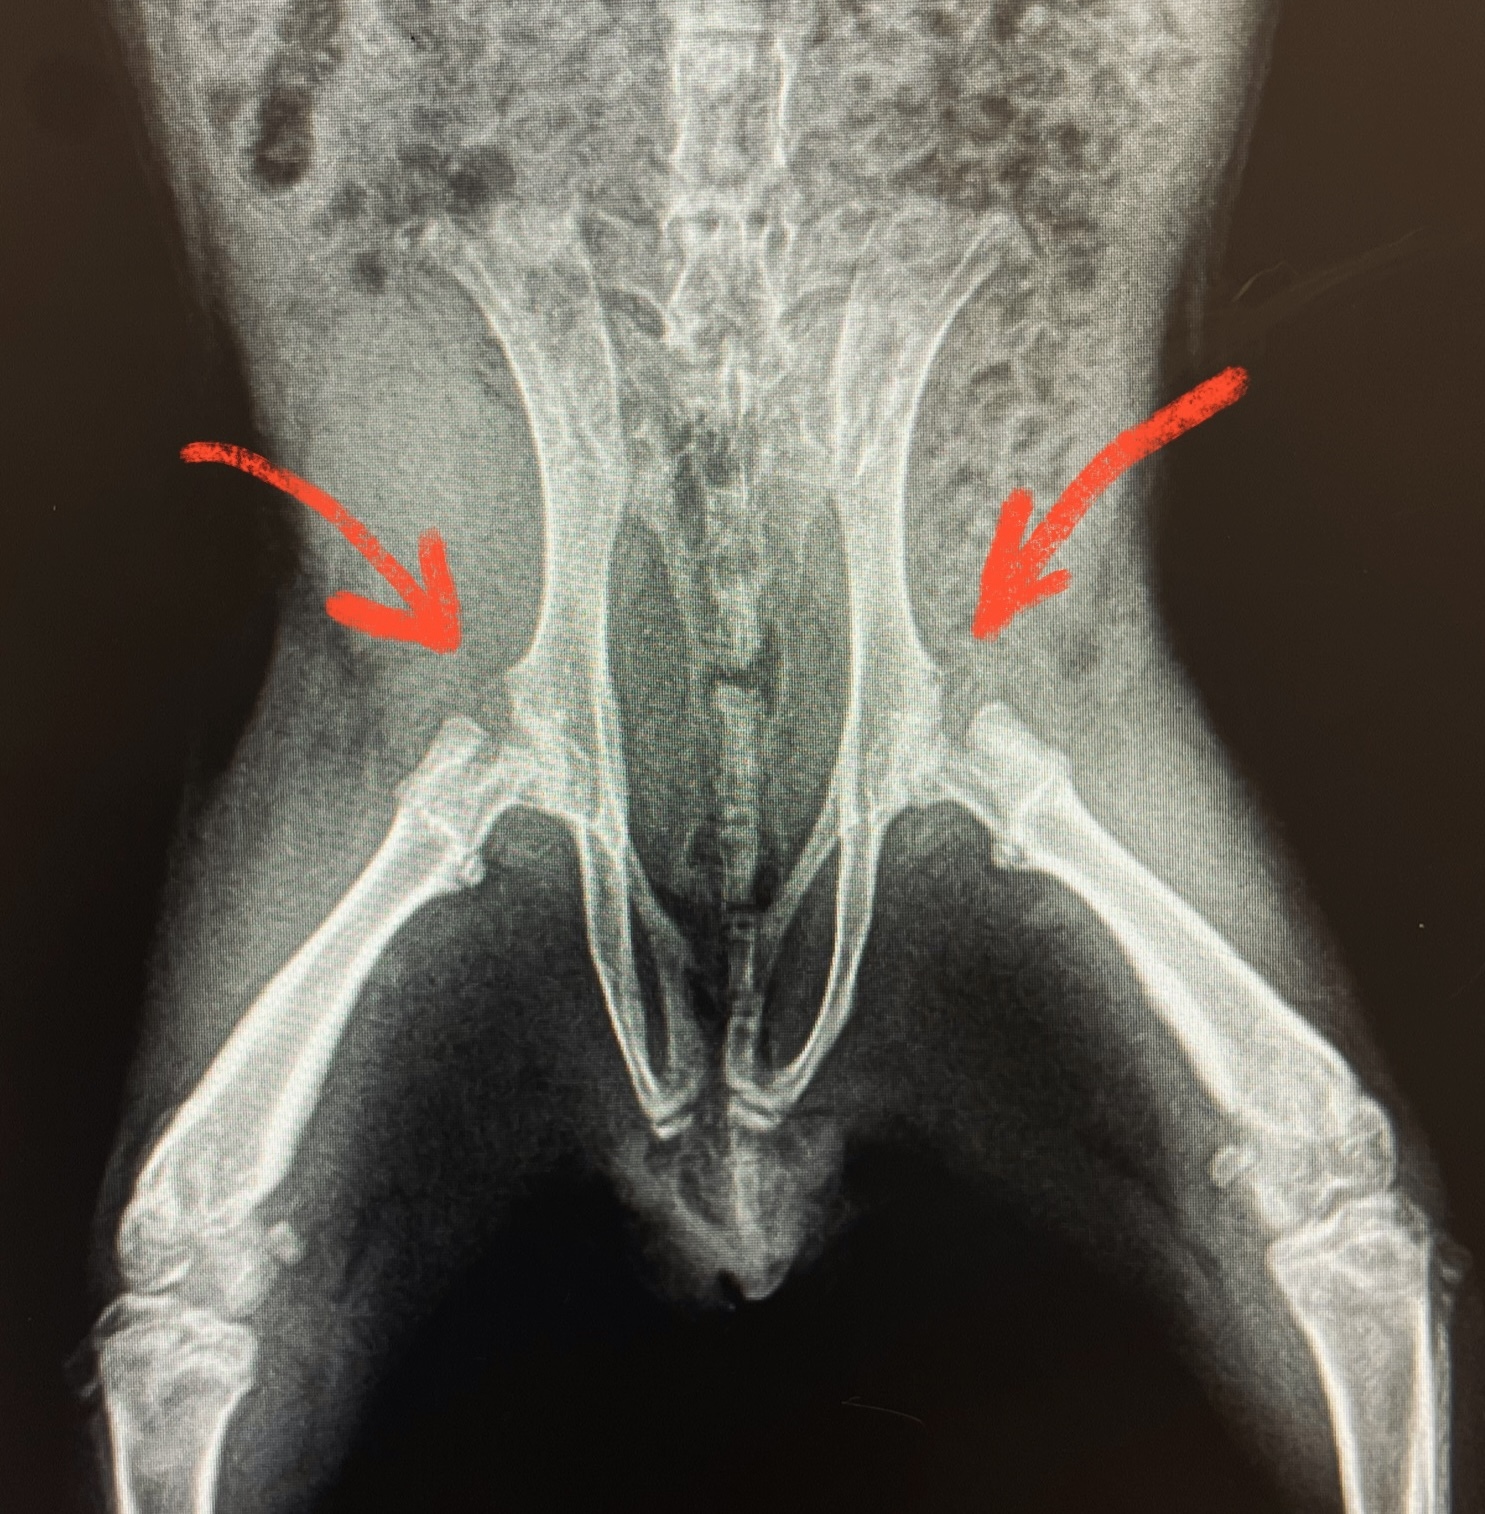

Прошло три недели. Сделали повторный рентген.

На радость всем, по костям пошли маленькие, но улучшения. Ноги остаются при свинке)

Оба с владельцем понимаем, что нужен рентген, и вновь он решающий. На лучшее я уже не надеюсь и морально готовилюсь сообщить плохие новости.

Заношу данные пациента в программу, выставляю параметры рентгена, фиксируем недовольную свинку. Щёлк, щёлк. Отдаю свинку ассистенту и напряжённо подхожу к компьютеру, чтобы рассмотреть снимки. Удивленно поднимаю брови.

- А неплохо, очень неплохо. Даже хорошо. Далеко не идеально, но для этого пациента вообще прекрасная динамика.